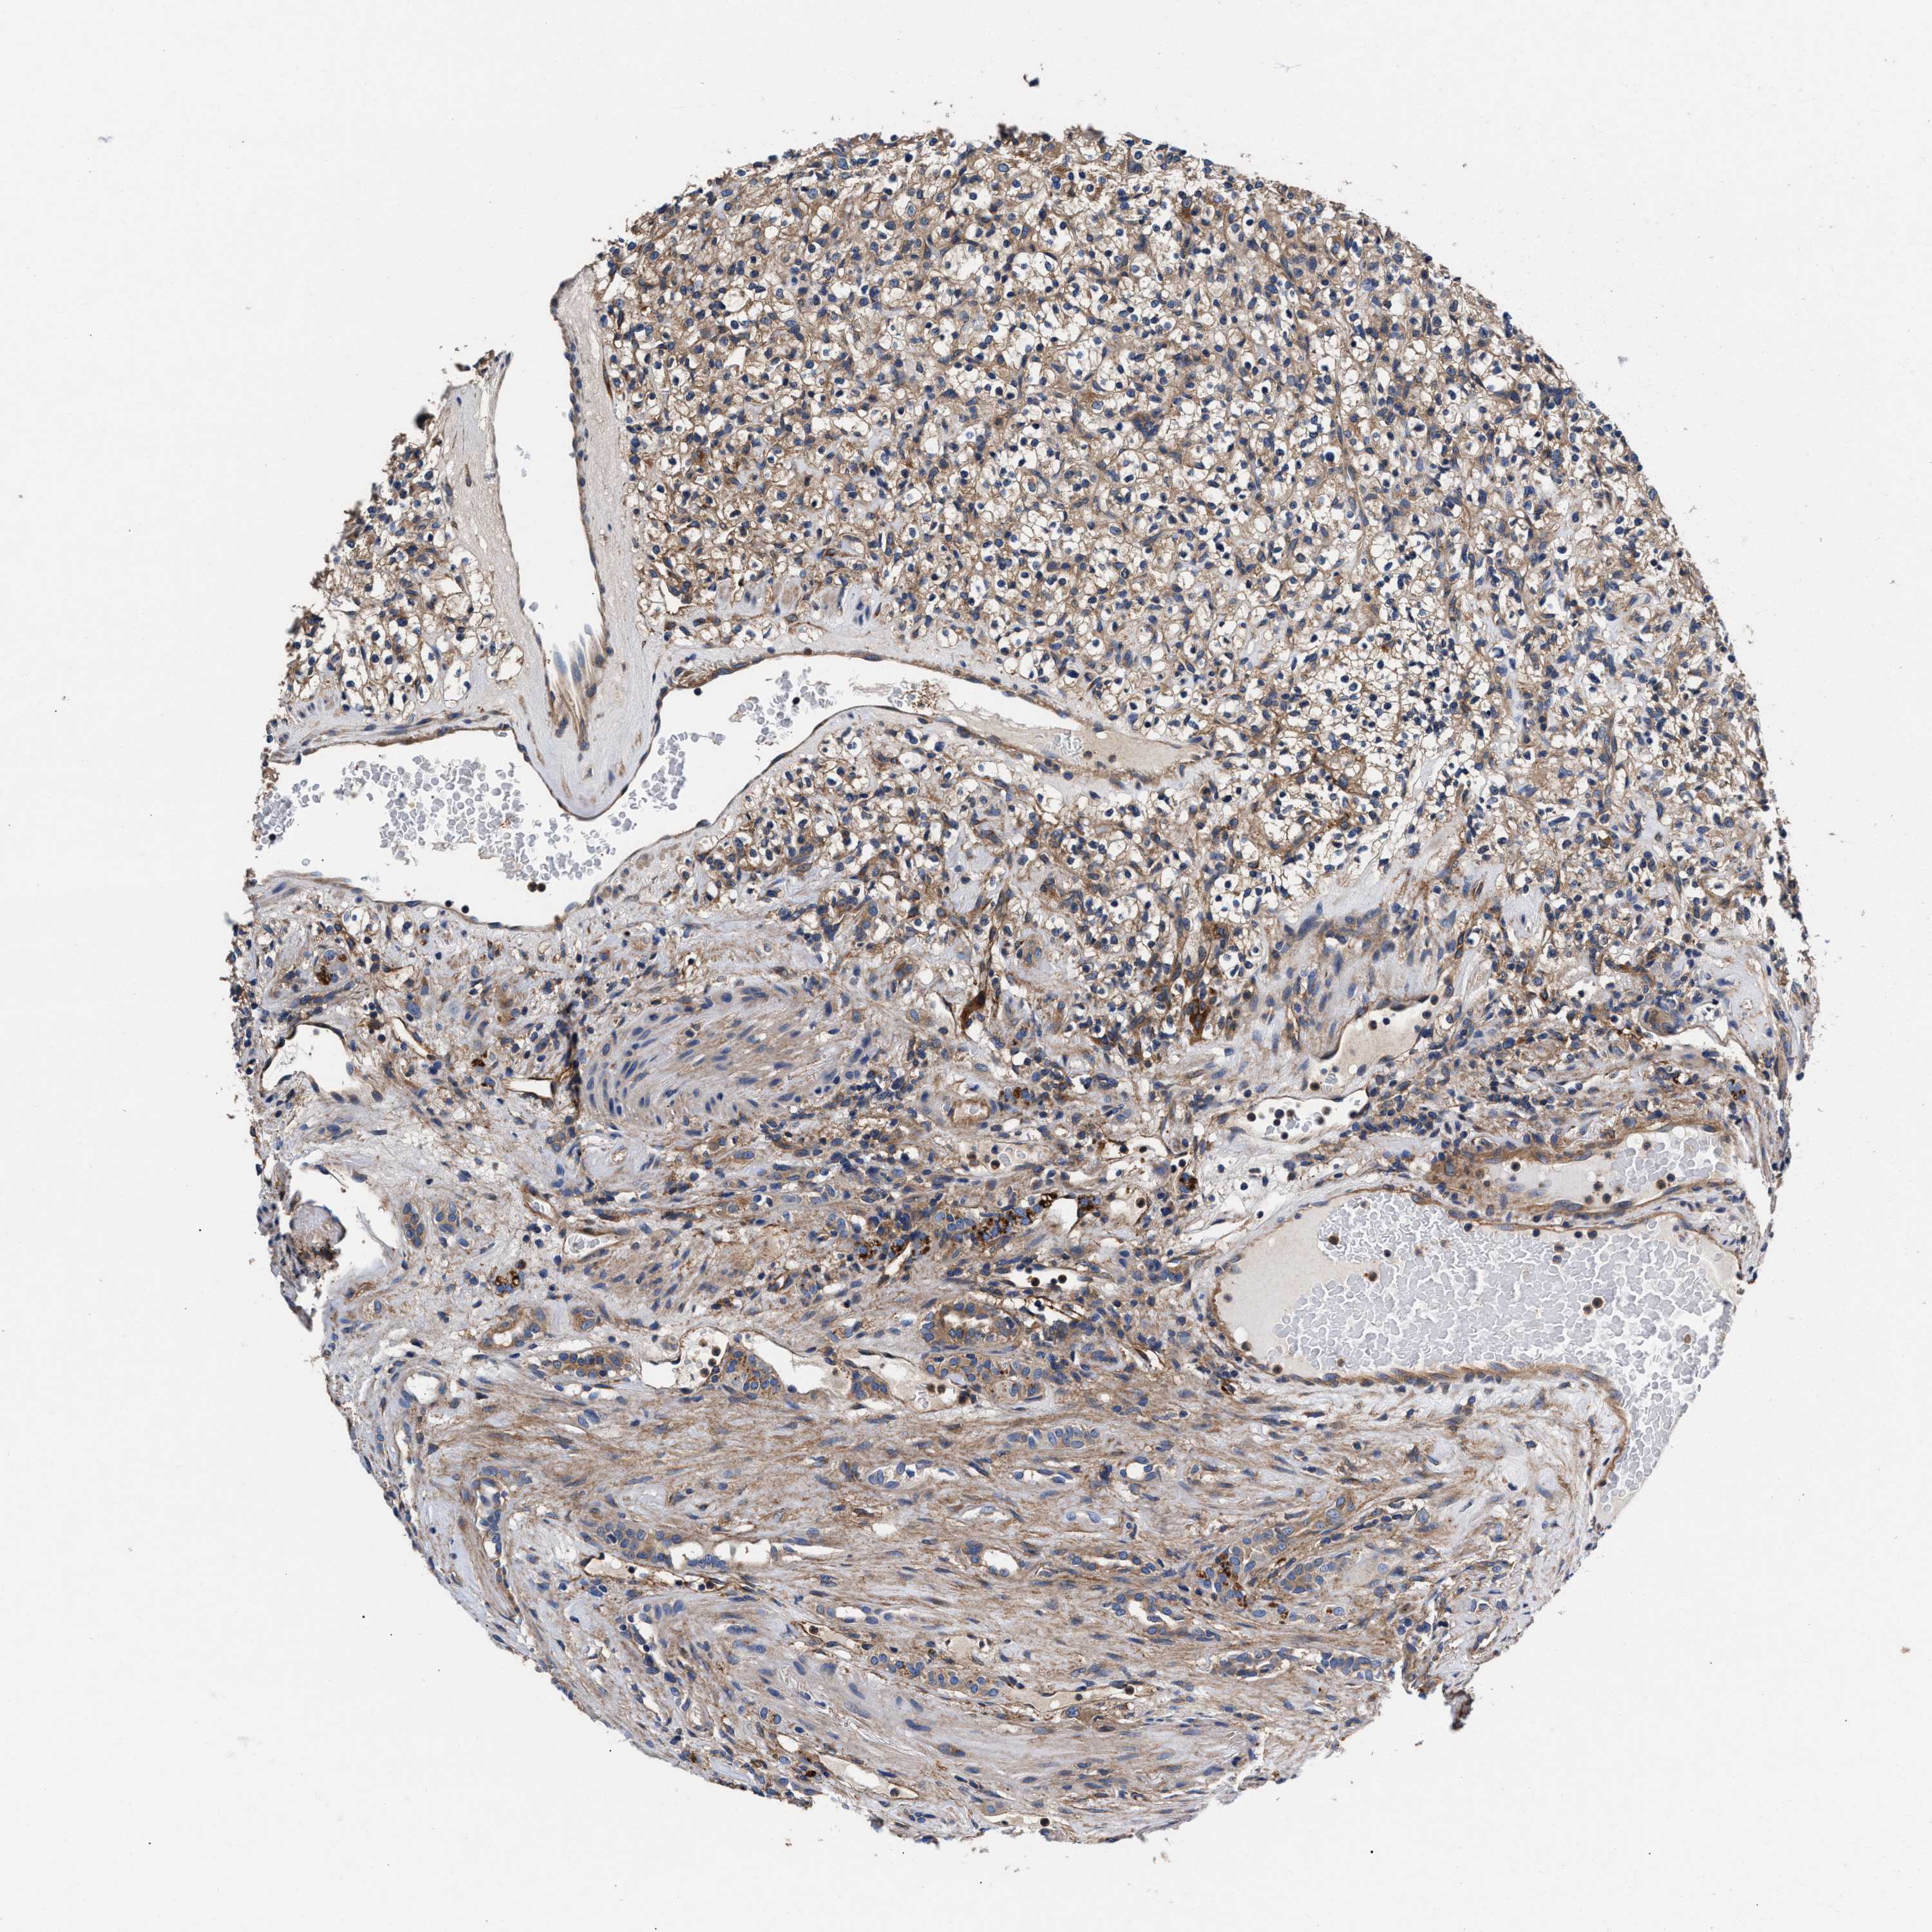

KIDNEY RENAL PAPILLARY CELL CARCINOMA (TCGA) - Interactive survival scatter ploti

The Survival Scatter plot shows the clinical status (i.e. dead or alive) for all individuals in the patient cohort, based on the same data that underlies the corresponding Kaplan-Meier plots. Patients that are alive at last time for follow-up are shown in blue and patients who have died during the study are shown in red.

The x-axis shows the expression levels (FPKM) of the investigated gene in the tumor tissue at the time of diagnosis. The y-axis shows the follow-up time after diagnosis (years). Both axes are complimented with kernel density curves demonstrating the data density over the axes. The top density plot shows the expression levels (FPKM) distribution among dead (red) and alive patients (blue). The right density plot shows the data density of the survived years of dead patients with high and low expression levels respectively, stratified using the cutoff indicated by the vertical dashed line through the Survival Scatter plot. This cutoff is automatically defined based on the FPKM cutoff that minimizes the p-score. The cutoff can be changed by dragging the vertical line or by entering a cutoff value in the square labeled "Current cut-off".

Under the Survival Scatter plot the p-score landscape (black curve; left axis) is shown together with dead median separation (red curve; right axis). Dead median separation is the difference in median mRNA expression between patients who have died with high and low expression, respectively. It is calculated as follows: median FPKM expression of dead patients with high expression - median FPKM expression of dead patients with low expression. This is intended to aid the user in visually exploring custom cutoffs and the associated p-scores and dead median separation.

Individual patient data is displayed and can be filtered by clicking on one or more of the category buttons on the top of the page. Categories describing expression level and patient information include: high, low, alive, dead, female, male and tumor stages. The scale of the x-axis can be toggled between linear and log-scale by clicking on the "x log" button. Mouse-over function shows TCGA ID, patient information and mRNA expression (FPKM) for each patient.

& Survival analysisi

Kaplan-Meier plots summarize results from analysis of correlation between mRNA expression level and patient survival. Patients were divided based on level of expression into one of the two groups "low" (under cut off) or "high" (over cut off). X-axis shows time for survival (years) and y-axis shows the probability of survival, where 1.0 corresponds to 100 percent.

SH3GL1 is not prognostic in Kidney Renal Papillary Cell Carcinoma (TCGA)

Best expression cut offi